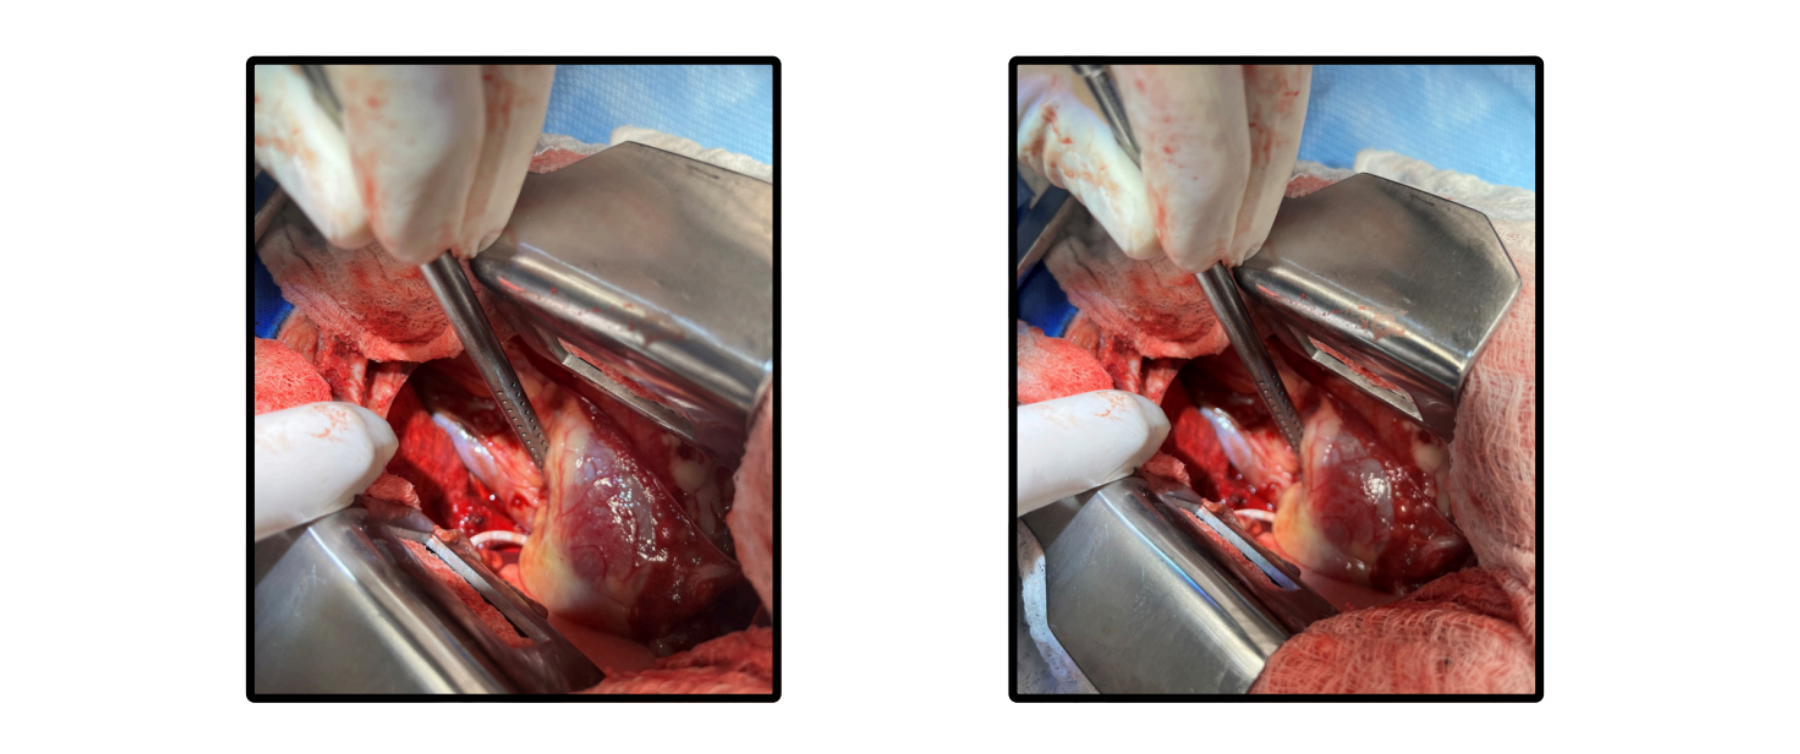

Procedure: Median sternotomy performed on 05-29-2024

A quill was located penetrating the right side of the cranial vena cava with additional quills in the pericardium.

A residual volume of frank blood was noted in the thoracic cavity, along with damage to the medial side of the right cranial lung lobe.

A ventral midline incision was made followed by an oscillating saw median sternotomy. Removal of the quill from the vena cava and exploratory thoracotomy were performed.

Closure utilized orthopedic wire and layered suturing techniques